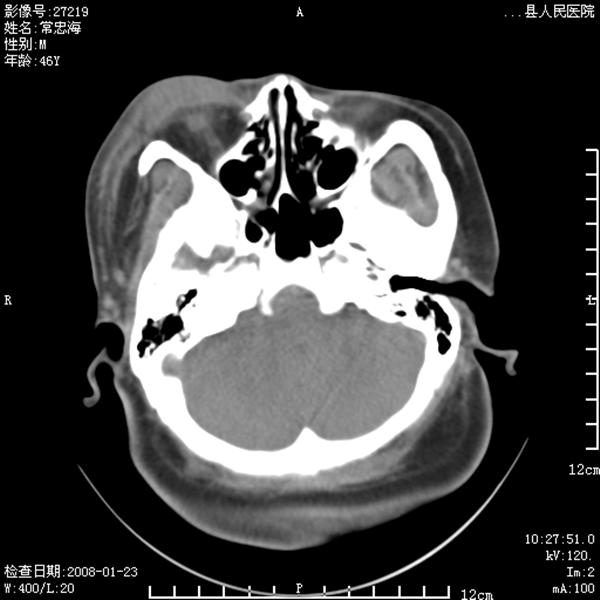

以下是引用江边学者在2008-4-19 22:26:00的发言:[br]1.胼胝体发育不良。[br]2.右侧眼球痨。[br]3.右侧颜面部软组织挫伤。